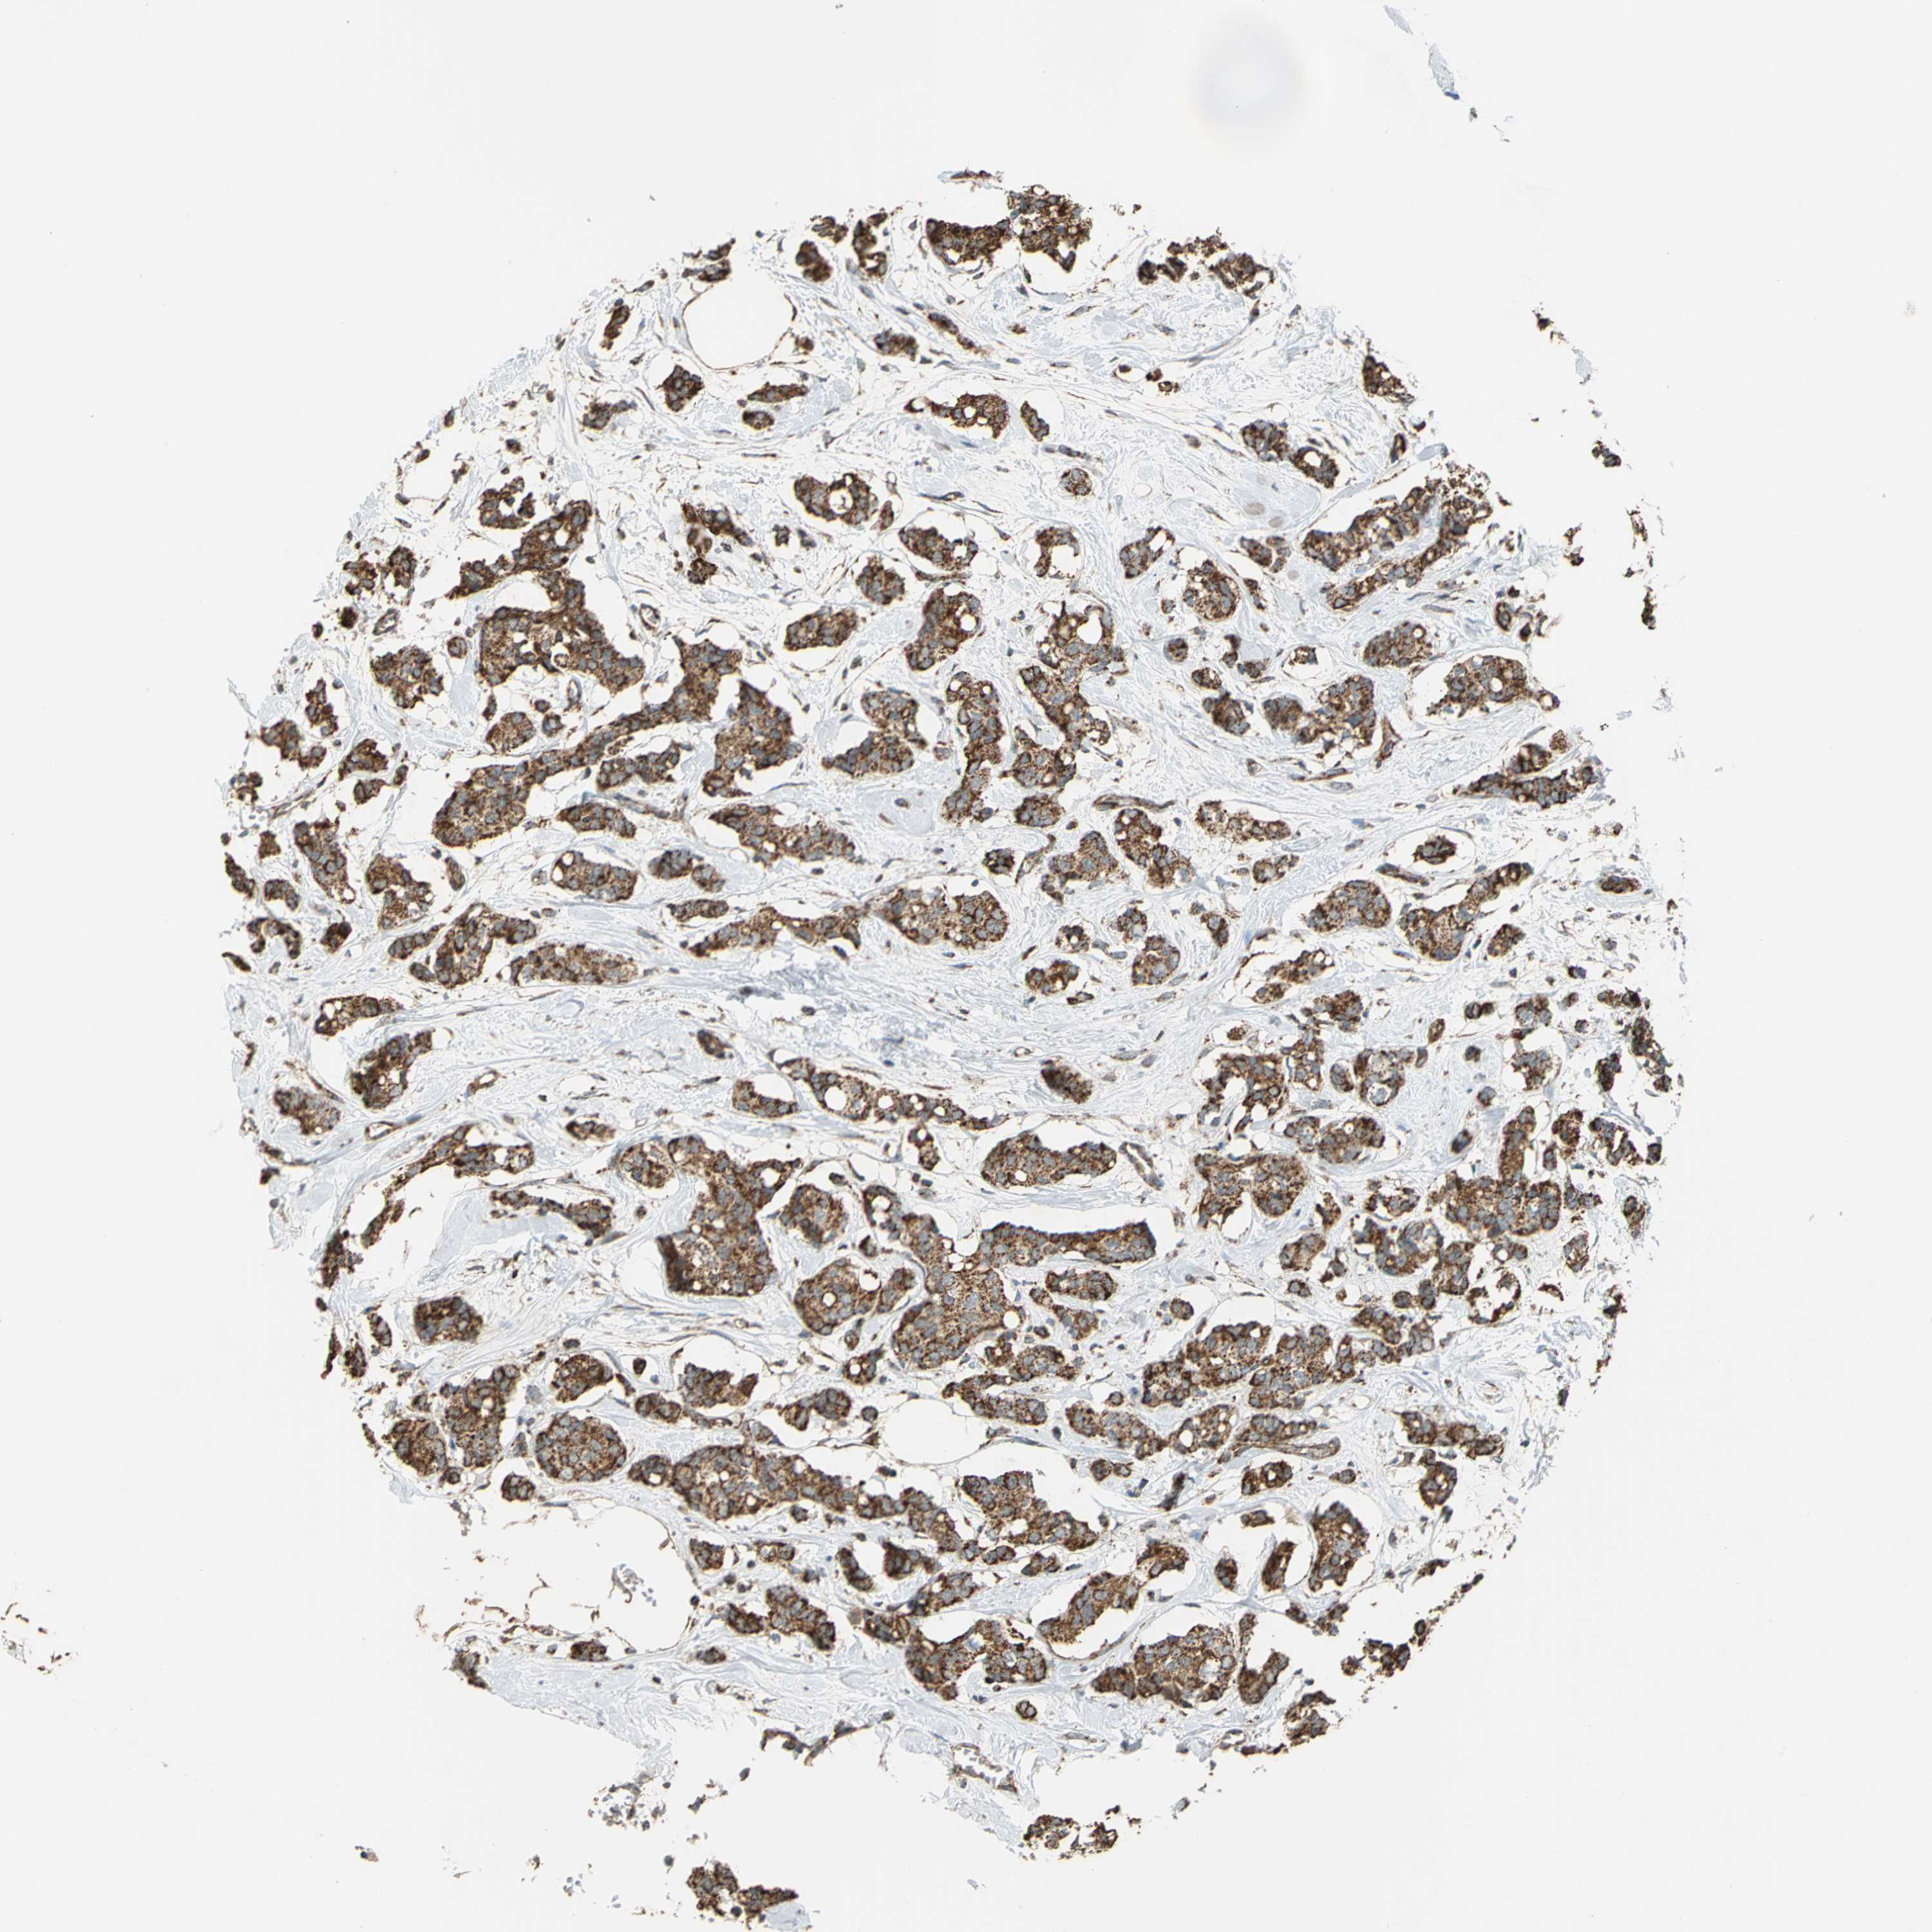

CANCER BREAST CANCER Show tissue menu

BRCA TCGA BRCA VALIDATION PROTEIN EXPRESSION